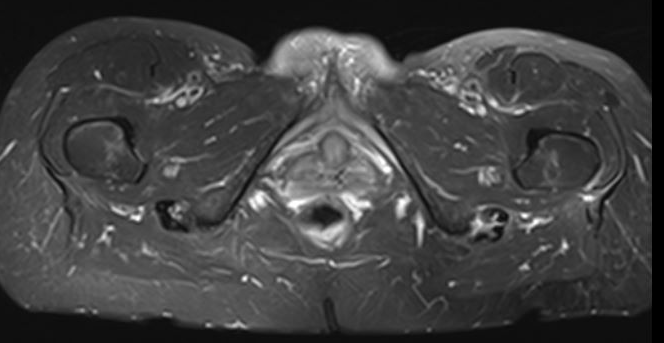

MRI

Peritendinous edema / low grade partial tears / tendinopathy

High grade partial tears